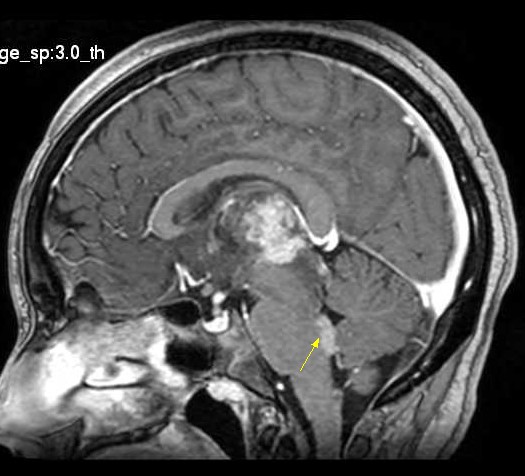

| Fem. 17a. |

| Nódulo sólido homogêneo preenchendo o III ventrículo, com limites precisos, com hipossinal em T1 e hipersinal em T2 e FLAIR, que se impregna por contraste paramagnético. Lesão menor implantada no assoalho do IV ventrículo provavelmente representa disseminação por via liquórica. |

| SAGITAIS, T1 SEM CONTRASTE | T1 COM CONTRASTE | |

| F. 17a. Tumor teratóide rabdóide atípico de III ventrículo. RM | HE | VIM, GFAP | HHF35, desmina, 1A4 | AE1AE3, EMA |